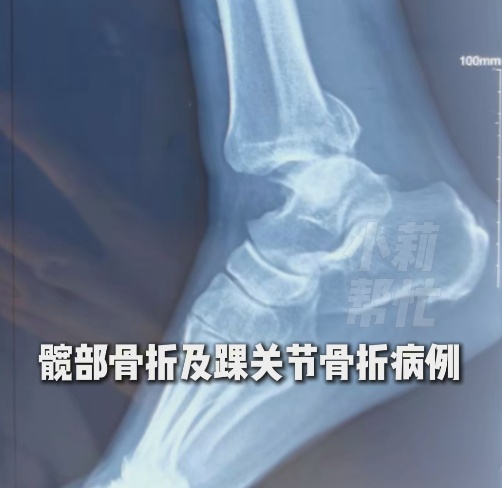

主治医师姜昊表示,因雨雪天摔倒而来就诊的患者伤情多集中于手腕、髋骨和踝关节骨折。其中,部分老年患者因骨质疏松,摔伤后需及时接受复位治疗或进一步治疗。